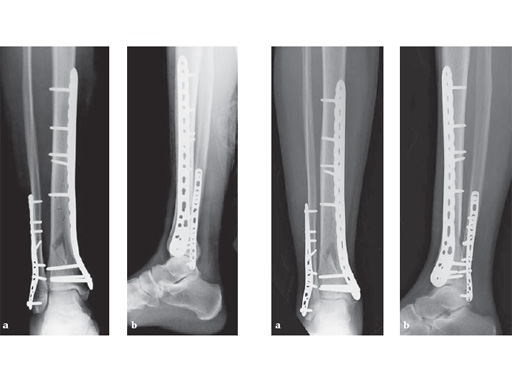

29-year-old female after a motor vehicel crash

Case provided by Sean Nork, Washington, USA

The fibula was reduced and stabilized through a posterolateral surgical approach. A small anterior incision was used to apply multiple clamps and to access the fracture reduction. A medial locked distal tibial plate was placed adjacent to the anteromedial surface of the tibia through a 4 cm distal incision. Multiple proximal screws were placed through small incisions overlying the plate.